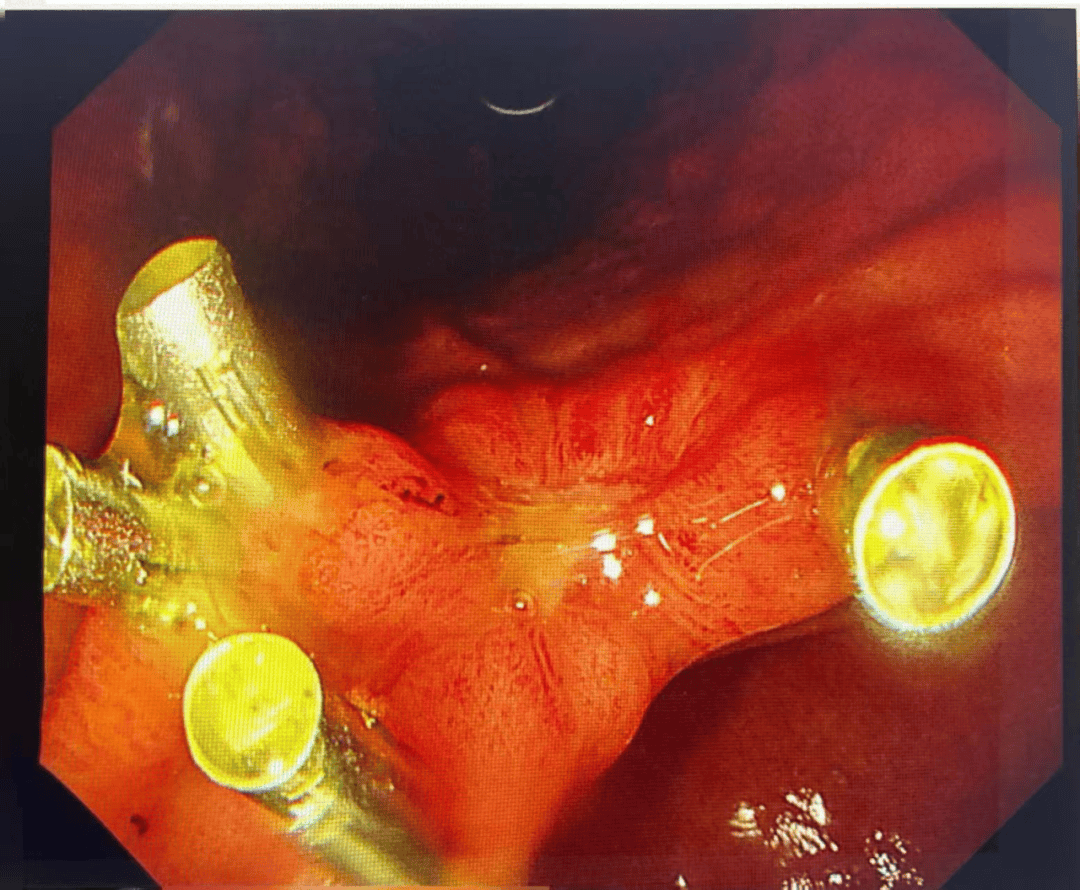

明确诊断后予抑酸、溶石、补液等对症处理,2周复查胃镜提示:胃多发溃疡(H1期)。胃底、胃体黏膜光光滑,胃石已溶解消除。

2025-12-25复查胃镜